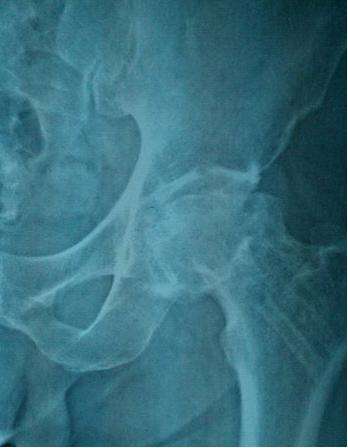

儿童股骨头坏死,又称股骨头骨骺软骨炎、股骨头无菌性坏死或扁平髋。是儿童常见的原因不明的软骨病,多发于2~12岁儿童,以退行性变或坏死开始,继后出现再生或重新钙化,最终出现股骨头的坏死。一开始表现为膝关节-髋关节痛,步行不便或跛行,患髋不能屈伸、内收。因为有的很隐匿,孩子只是有点疼,跛行两天,有像是没事了,只有磁共振才能发现股骨头的缺血水肿,本病早期诊断早期治疗十分重要,但又有几个家长愿意让孩子因为髋关节有点疼痛就去做磁共振呢?

非手术治疗:非手术治疗主要用于年龄<6岁,CatterallⅠ-Ⅱ型的患儿。方法有卧床休息、外展位牵引、石膏固定、外展支架或矫形器矫正等,这些支具需下肢外展40°-45°,内旋10°-15°或无内旋,以期获得包容,防止脱位。佩戴支具后髋、膝关节可自主活动,这不仅有利于股骨头形态的重塑和保持良好的活动范围,且能促进关节滑液的流动,有利于软骨和滑膜的营养。

儿童股骨头坏死没有被正常的治疗或正常的治疗延误以后致残风险是很高的,治疗的预后跟发病的年龄,治疗方式的干预是否恰当,是否及时的是相关的,发病在六七岁以后,及时的进行手术治疗能够有效的避免股骨头发生严重的致残类型,如果已经延误治疗也有一些手术方法,可以把残疾的程度降到最低。